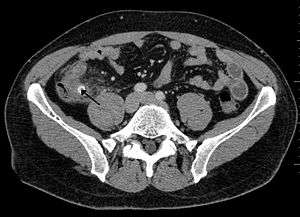

Computed tomography

Where it is readily available, computed tomography (CT) has become frequently used, especially in people whose diagnosis is not obvious on history and physical examination. Concerns about radiation tend to limit use of CT in pregnant women and children, especially with the increasingly widespread usage of MRI.[47][48]

The accurate diagnosis of appendicitis is multi-tiered, with the size of the appendix having the strongest positive predictive value, while indirect features can either increase or decrease sensitivity and specificity. A size of over 6 mm is both 95% sensitive and specific for appendicitis.[49]

However, because the appendix can be filled with fecal material, causing intraluminal distention, this criterion has shown limited utility in more recent meta analyses.[50] This is as opposed to ultrasound, in which the wall of the appendix can be more easily distinguished from intraluminal feces. In such scenarios, ancillary features such as increased wall enhancement as compared to adjacent bowel and inflammation of the surrounding fat, or fat stranding, can be supportive of the diagnosis, although their absence does not preclude it. In severe cases with perforation, an adjacent phlegmon or abscess can be seen. Dense fluid layering in the pelvis can also result, related to either pus or enteric spillage. When patients are thin or younger, the relative absence of fat can make the appendix and surrounding fat stranding difficult to see.[50]